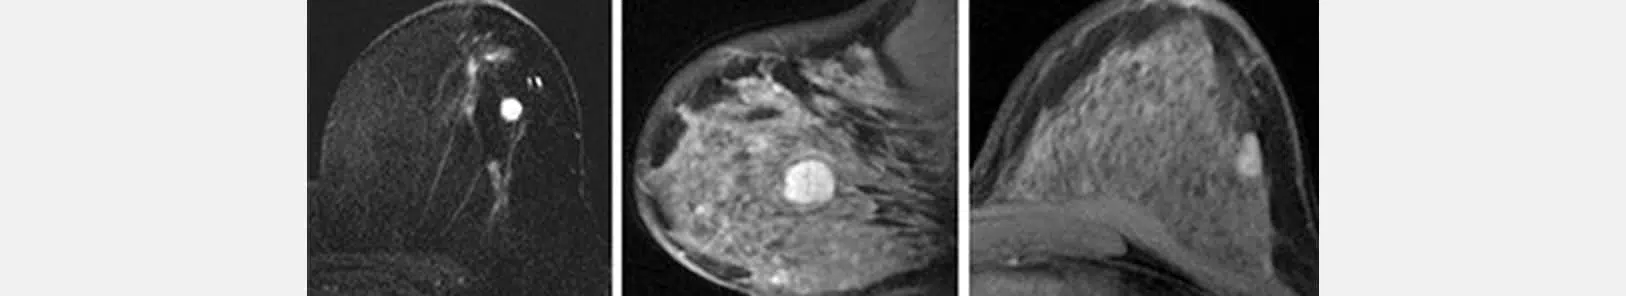

التصوير بالرنين المغناطيسي (IRM)

لا يحل التصوير بالرنين المغناطيسي محل التصوير الشعاعي للثدي أو الموجات فوق الصوتية، كما أنه لا يُعدّ فحصًا منهجيًا، سواء للكشف أو لتشخيص سرطان الثدي.

إنه فحص يُوصف أحيانًا من قبل الطبيب في الحالات التالية:

- في إطار الفحص لدى بعض المريضات المعرضات لخطر مرتفع للإصابة بالسرطان (بسبب طفرة جينية).

- في حالة الاشتباه في وجود سرطان، للمساعدة في التشخيص عندما لا تسمح الفحوصات التقليدية بالتوصل إلى نتيجة مؤكدة.

- في حالة السرطان المؤكد، لتحديد مدى انتشار الآفات بشكل أدق.

- أثناء العلاج، خاصة في حالة العلاج الكيميائي قبل الجراحة.

بالنسبة للنساء غير المُنقطع عندهن الطمث، يُفضل إجراء التصوير بالرنين المغناطيسي بين اليوم الثامن والثاني عشر من الدورة الشهرية.

أما بالنسبة للنساء في سن اليأس اللواتي يتبعن علاجًا هرمونيًا تعويضيًا، فيوصى بالتوقف عن هذا العلاج قبل 6 إلى 8 أسابيع من الفحص.

التصوير بالرنين المغناطيسي غير إشعاعي وغير مؤلم.